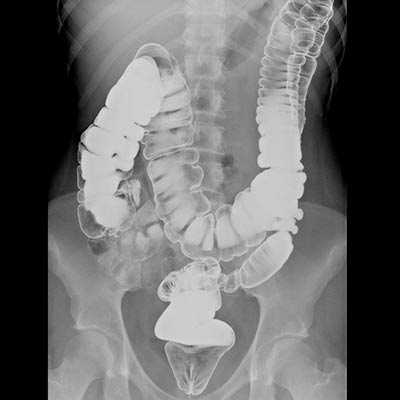

Как диагностируют рак кишечника с метастазами?

Обычно первичную опухоль обнаруживают с помощью колоноскопии — эндоскопического исследования, во время которого в толстую кишку через задний проход вводят специальный инструмент — колоноскоп. Если во время колоноскопии выявлено патологическое образование, врач получает фрагмент ткани из него и отправляет в лабораторию для изучения под микроскопом, молекулярно-генетического анализа. Этот метод диагностики называется биопсией, он помогает окончательно подтвердить диагноз.

Когда рак кишки подтвержден, применяют разные исследования для поиска метастазов в брюшной полости и за ее пределами:

- КТ, МРТ

- УЗИ органов брюшной полости

- ПЭТ-сканирование

- Рентгенографию грудной клетки

- Бронхоскопию

- Рентгенографию костей

- Ангиографию печени

- При необходимости проводят диагностическую лапароскопию